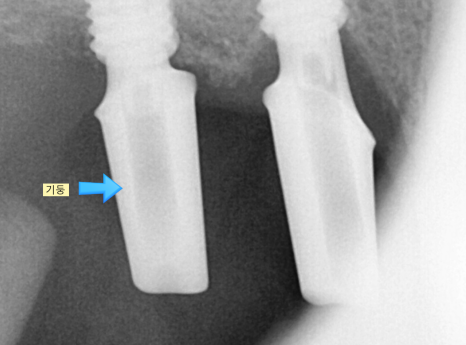

240315 머리를 올리는 작업

흔히 임플란트는 위에 씹는 기능을 수행하는 머리 부분이라 생각하시지만

치아 뿌리를 대체하는 것이 임플란트입니다.

때문에 머리를 만들어 주기 위해서는

임플란트와 머리를 연결해주는 중간 기둥을 넣고

뽄을 뜨는 작업을 시행하는데요.

위아래 임플란트 수술도 동시에

머리 만드는 작업도 한번에 해주었습니다.